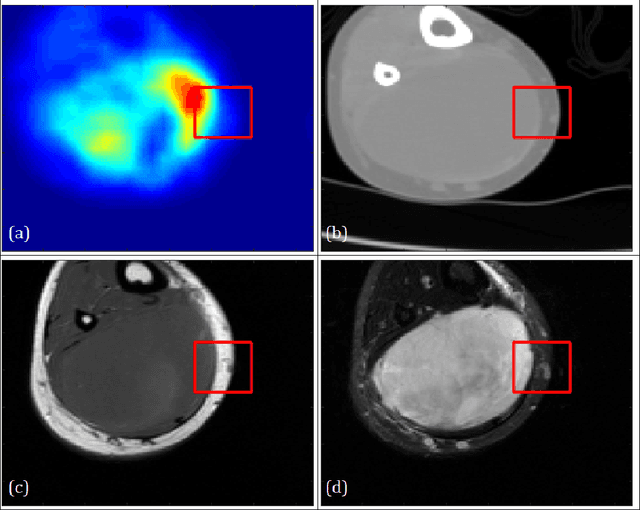

Abstract:Image analysis using more than one modality (i.e. multi-modal) has been increasingly applied in the field of biomedical imaging. One of the challenges in performing the multimodal analysis is that there exist multiple schemes for fusing the information from different modalities, where such schemes are application-dependent and lack a unified framework to guide their designs. In this work we firstly propose a conceptual architecture for the image fusion schemes in supervised biomedical image analysis: fusing at the feature level, fusing at the classifier level, and fusing at the decision-making level. Further, motivated by the recent success in applying deep learning for natural image analysis, we implement the three image fusion schemes above based on the Convolutional Neural Network (CNN) with varied structures, and combined into a single framework. The proposed image segmentation framework is capable of analyzing the multi-modality images using different fusing schemes simultaneously. The framework is applied to detect the presence of soft tissue sarcoma from the combination of Magnetic Resonance Imaging (MRI), Computed Tomography (CT) and Positron Emission Tomography (PET) images. It is found from the results that while all the fusion schemes outperform the single-modality schemes, fusing at the feature level can generally achieve the best performance in terms of both accuracy and computational cost, but also suffers from the decreased robustness in the presence of large errors in any image modalities.